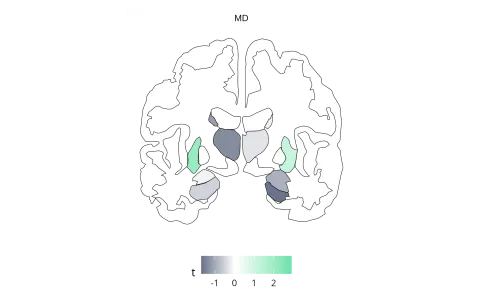

“Our findings indicate that a high consumption of ultra-processed foods is associated with structural changes in brain regions regulating eating behaviour, such as the hypothalamus, amygdala and right nucleus accumbens. This may lead to a cycle of overeating. However, long-term and experimental studies are still needed to strengthen the association,” says doctoral researcher  Arsène Kanyamibwa of the University of Helsinki.